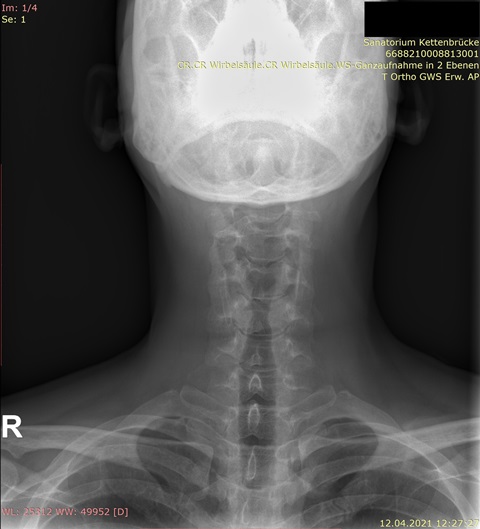

Bei Männern mit "leichter" Skoliose kommt es nicht selten vor, dass ein Rundrücken und Hohlkreuz das eigentliche Problem sein kann. Deshalb braucht man auch immer ein Röntgenbild der gesamten Wirbelsäule von vorn und eins von der Seite, wo man das erkennen kann.

Habe die Bilder. Für mich als Laie sieht es nicht so schlimm aus auf den Röntgenaufnahmen, aber ich bin in der Realität total asymmetrisch und schief, und am extremsten ist, dass die Rippen/Brustkorb auf der rechten Seite viel mehr rausstehen und das optisch sehr auffällt.

Im Anhang die Bilder.

Ich (auch Laie) sehe nur eine geringe Seitabweichung der Wirbelsäule, aber eine deutliche Rotation, erkennbar an den "Kringeln" der Dornfortsätze und Querfortsätze. Ich denke auch, dass da ein Spezialist gefragt ist.rudi777 hat geschrieben: ↑Do, 22.04.2021 - 16:20 Für mich als Laie sieht es nicht so schlimm aus auf den Röntgenaufnahmen, aber ich bin in der Realität total asymmetrisch und schief, und am extremsten ist, dass die Rippen/Brustkorb auf der rechten Seite viel mehr rausstehen und das optisch sehr auffällt.